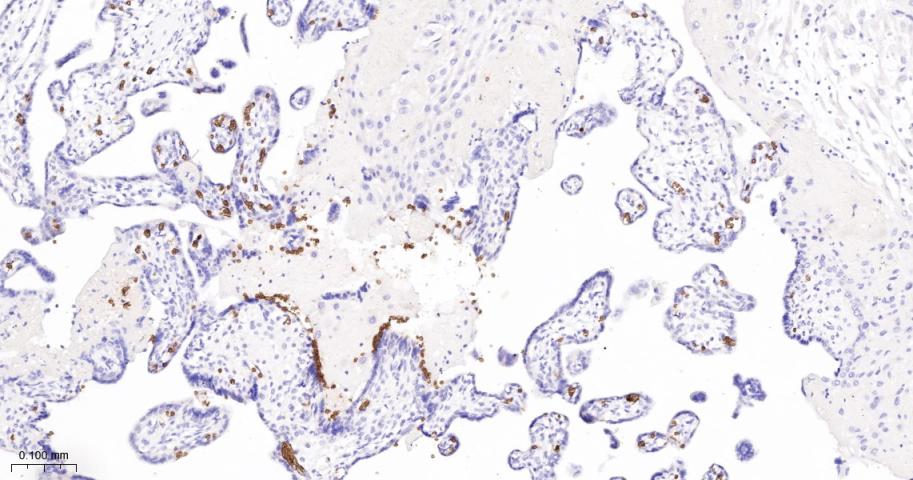

Paraformaldehyde-fixed, paraffin embedded Human Placenta; Antigen retrieval by boiling in sodium citrate buffer (pH6.0) for 15 min; The section was incubated with Glycophorin A Monoclonal Antibody, Unconjugated (bsm-61632R) at 1:200 overnight at 4°C, followed by conjugation to the bs-0295G-HRP and DAB (C-0010) staining.